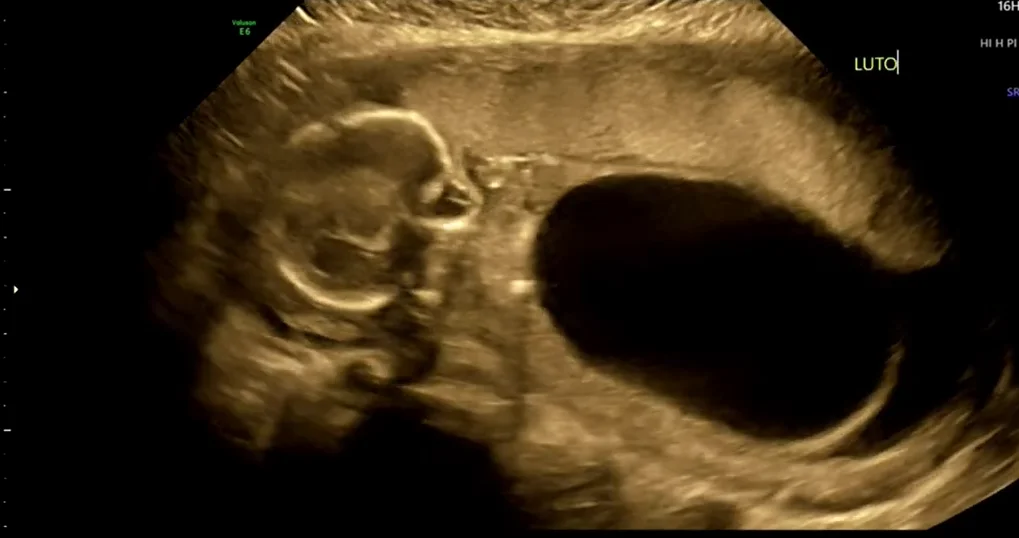

Van niệu đạo sau ở thai nhi (Posterior Urethral Valves - PUV)

• Bàng quang to (Megacystis) và tắc nghẽn đường tiết niệu dưới (Lower urinary tract obstruction)

• Van niệu đạo sau ở thai nhi (Posterior Urethral Valves - PUV)